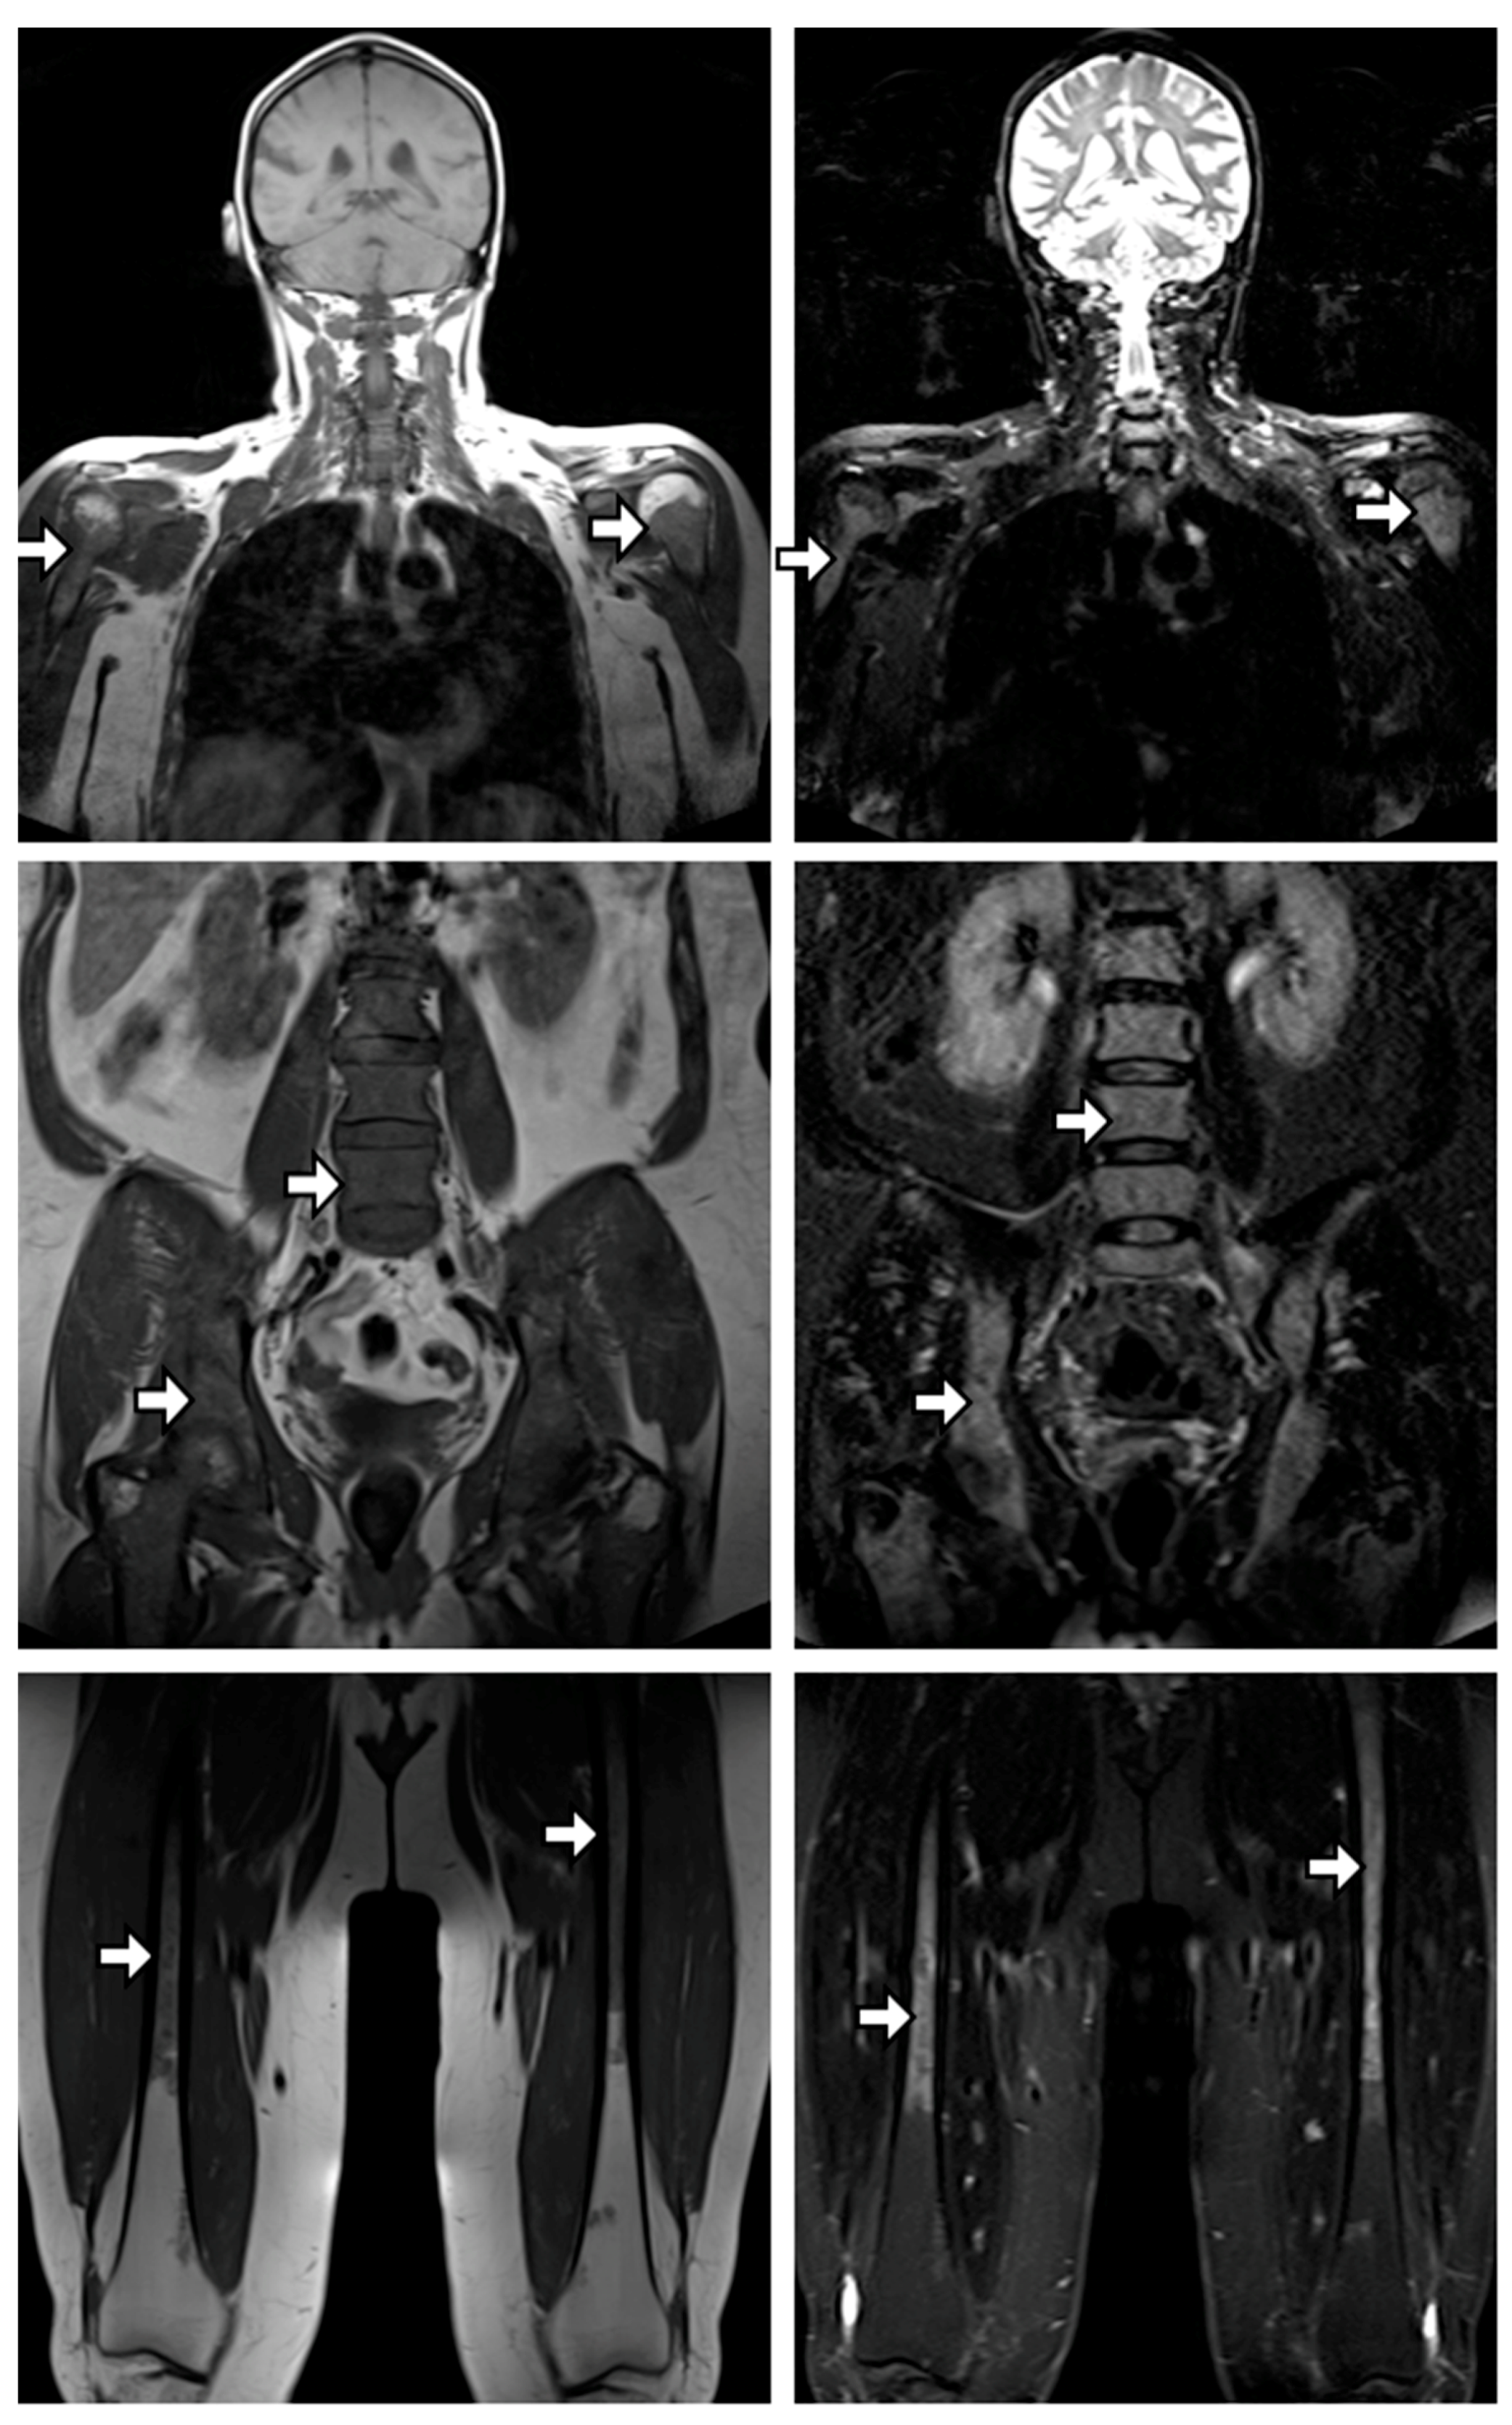

3.1. Spatial Heterogeneity in Local Growth Dynamics

4.1. Spatial Heterogeneity in Growth Dynamics between Different Focal Lesions